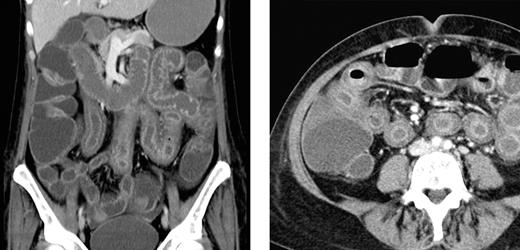

The severity of symptoms in patients varied largely and ranged from subtle and slowly progressive in the index patient to severe in 2 patients with high-dose carmustine, etoposide, cytarabine, and melphalan (BEAM) chemotherapy and autologous HSCT. In 1 of these latter 2 patients, bowel perforation was suspected because of severe abdominal pain and tenderness. In this particular patient, an abdominal computed tomography (CT) scan disclosed extensive and pronounced edema of the small bowel sparing other parts of the gastrointestinal tract (Figure 2). A similar small bowel edema was seen in a CT series in another patient who developed NV-GE with acute abdomen after high-dose methotrexate-based polychemotherapy. The other patient with BEAM chemotherapy and autologous HSCT experienced continuous retching, which was refractory to intensified antiemetic therapy. Unfortunately, this patient experienced severe aspiration resulting in hypoxic brain damage and death 11 days after onset of NV-GE. Another 2 patients experienced fatal sepsis 17 and 49 days after onset of symptoms of NV-GE. The first of these latter 2 patients showed profound neutropenia (neutrophil count, 0.03/nL) after intensified chemotherapy for acute myeloid leukemia and at the onset of NV-GE. Subsequently, this patient experienced fatal sepsis despite broad-spectrum antibacterial and antifungal therapy (repetitive blood cultures were negative). In the other patient, who had received allogeneic HSCT 2 months before the NV infection, Escherichia coli was repeatedly recovered from the blood stream without any clinical site of infection, suggesting that bacterial translocation from the intestine was promoted by the NV infection.

Abdominal CT scan of a patient with NV GE. Extensive bowel edema in a patient with NV GE acquired during BEAM conditioning chemotherapy for autologous HSCT. The bowel wall edema was restricted to the small intestine, and the colon showed only a moderate dilation.

We found a significantly prolonged duration of symptoms in patients compared with staff members, which clearly confirms findings from previously published, noncomparative reports on patients with various immunocompromising conditions and NV-GE.13-17 In this outbreak, the maximum duration of symptoms among patients was limited to 36 days, but profuse diarrhea with wasting lasting up to more than 1 year has been previously observed in allogeneic HSCT patients with delayed diagnosis of NV-GE.14 Of importance, we observed severe-to-fatal complications, which were clearly attributable or likely caused by the NV infection. Two patients with BEAM chemotherapy developed symptoms of an acute abdomen with peritonitis, which prompted abdominal CT scans showing extensive and pronounced bowel wall edema restricted to the small intestine.

This radiologic pattern is identical to previous observations in a small number of nonimmunocompromised patients with NV-GE.26,27 However, BEAM chemotherapy, gastrointestinal CMV infection, or GVHD might also cause small bowel edema, but exclusive involvement of the small intestine has been observed infrequently in intestinal CMV infection or GVHD, and radiologic studies in patients with gastrointestinal complications after BEAM chemotherapy (eg, colitis and stomatitis) are missing.28,29 The coexistence of NV infection and intestinal GVHD could represent a diagnostic and therapeutic challenge. We found evidence of simultaneous GVHD in large bowel biopsies in a single patient with NV-GE. It appears less likely that the GVHD-like pattern in this particular patient was directly caused by the NV as studies in healthy volunteers with experimental NV-GE showed unremarkable rectal biopsies.30 However, we found no evidence of small intestine GVHD coexisting with NV infection in any of our patients.